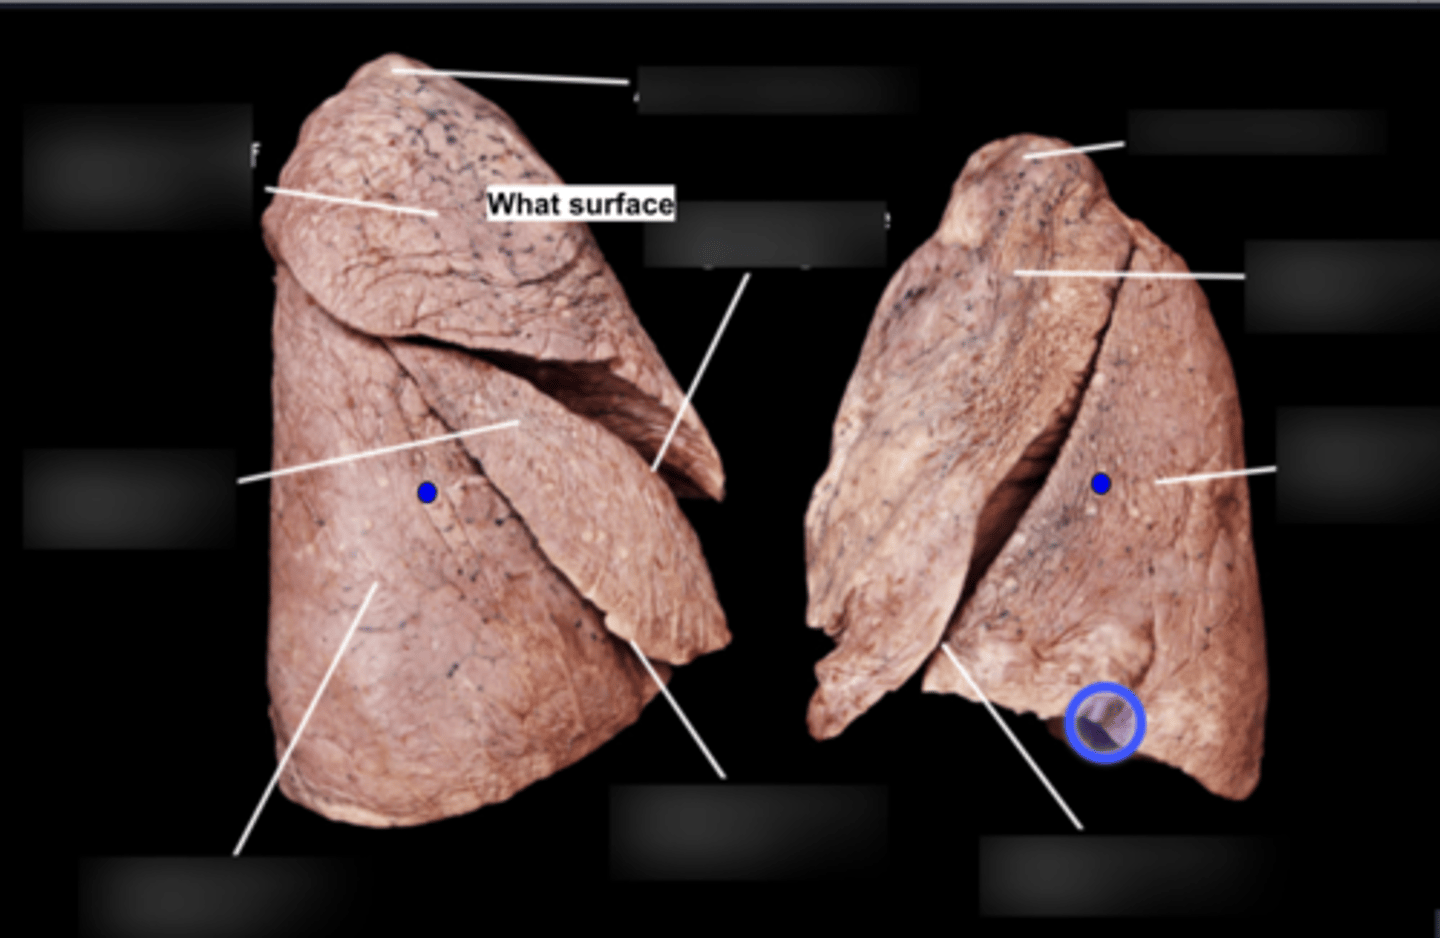

Superior lobe of right lung

Middle lobe of right lung

Inferior lobe of right lung

Superior lobe of left lung

Inferior lobe of left lung

Lingula

Apex

Base/Diaphragmatic Surface

Costal Surface

Mediastinal Surface

Anterior Margin

Posterior Margin